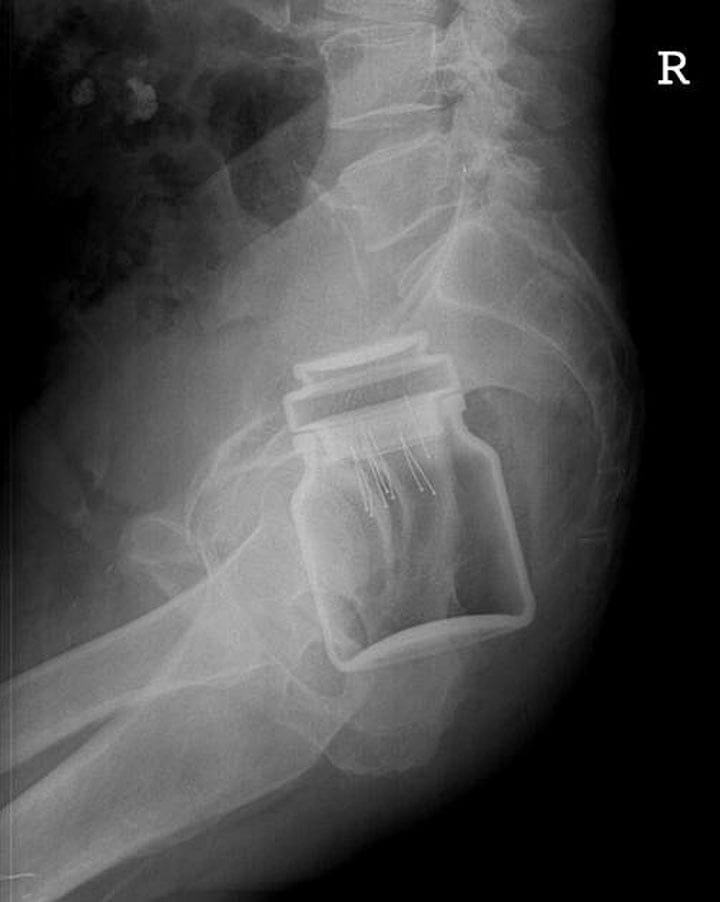

2. Оказывается, банки от аэрозолей врачи извлекают из задних проходов довольно часто